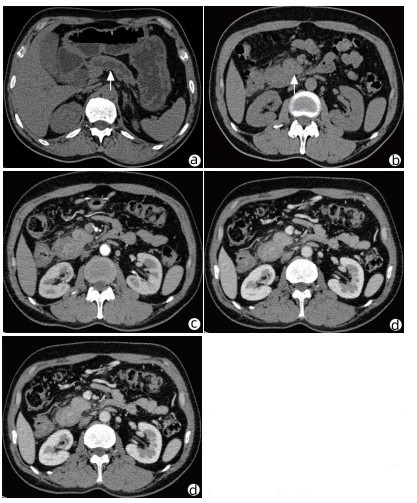

Acute pancreatitis caused by a hematoma in the duodenal wall: A case report

Mengran ZHU, Shanshan JIANG, Tingting YU, Yun BAI, Dingxin WANG, Linping SHI

2022, 38(3): 639-642. DOI: 10.3969/j.issn.1001-5256.2022.03.029

Abstract(1350) HTML (248) PDF (3475KB)(62)

Abstract: